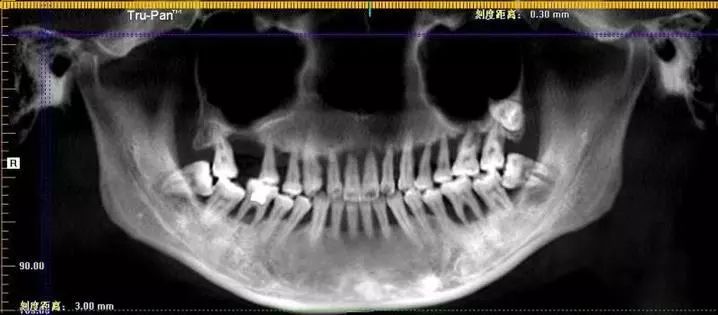

△牙片中清晰可见小萌的上口牙已摇摇欲坠

据悉,小萌的牙齿大部分有不同程度的松动,近几年来,已逐渐丧失了咀嚼功能,她一日三餐只能吃点软的或是糊的东西,偶尔嘴馋时喝点肉汤或是吞块肉,早已不知道吃肉是什么味道。每次跟同事聚餐,她基本都不动筷子,就稍微喝点汤羹意思一下,大家招呼她多吃点,她只能尴尬地笑笑说:“减肥。”

医生说,导致小萌半口多牙松动至功能丧失的是重度牙周炎。医生检查后,也很震惊:“上排的牙齿已经几乎是悬在口内了,明明才28岁,但你说她80岁,甚至90岁都不为过。90后缺单颗或者多颗牙的不算少见,但像小陶这么严重的我还是第一次碰上。”